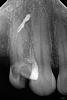

makdoc@bk.ru Опубликовано 16 декабря, 2010 Автор Поделиться Опубликовано 16 декабря, 2010 предположительно-это артефакт от лечения удаленного зуба,который накладывается в проекцию 2.5 зубавот ещё: Ссылка на комментарий

anastasiya.barhatova Опубликовано 16 декабря, 2010 Поделиться Опубликовано 16 декабря, 2010 Мне не нравится пломбировка каналов.И судя по двум другим снимкам - это всё-таки не последствия травмы. Ссылка на комментарий

DokDent Опубликовано 16 декабря, 2010 Поделиться Опубликовано 16 декабря, 2010 Мне не нравится пломбировка каналов.И судя по двум другим снимкам - это всё-таки не последствия травмы.+100!Отдалённый результат-прогноз сомнительный Ссылка на комментарий

DokDent Опубликовано 16 декабря, 2010 Поделиться Опубликовано 16 декабря, 2010 скорее всего это остаток пломбировочного материала, вышедшего из 5-го, которого уж нет.На прогноз 4-ки вряд ли влияет.А я имею ввиду обтурацию каналов 4-ки Ссылка на комментарий

Dr.Ru Опубликовано 17 декабря, 2010 Поделиться Опубликовано 17 декабря, 2010 так, терапевты мои взбунтовались и требуют опровержения озвученной мною предыдущей версии по поводу инопланетного вмешательстваони тоже предполагают что это вышедший материал из 5-ки, при чем скорее всего из перфорации Ссылка на комментарий

makdoc@bk.ru Опубликовано 17 декабря, 2010 Автор Поделиться Опубликовано 17 декабря, 2010 Доброго здоровья всем докторам, кто помог советом и ответом на вопрос "что делать?",отдельное спасибо докторам превратившим эту ветку в смехопанораму...надеюсь вы к своим пациентам так не относитесь...я живу далеко от столицы, не в областном ,а в районном центре, КТ у нас в городе нет,в областном городе эта процедура стоит от 3000руб,за лечение этого зуба я заплатила 1400руб (для меня немаленькие деньги)врач, которая это делала, сказала что это сросшийся перелом и запломбировать каналы дальше не представляется возможным...а про отдалённые результаты...поживём увидим...отпишусь. Ссылка на комментарий